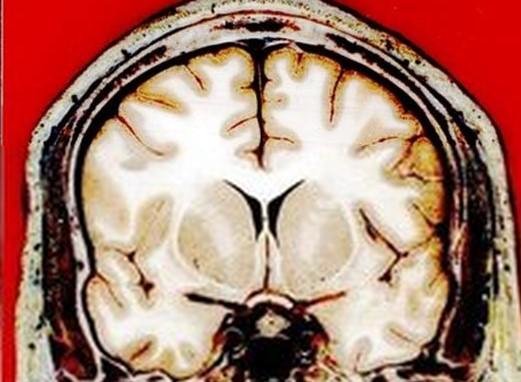

首先,我们看到,科学家们已经在记录梦的影像方面迈出了第一步, 在未来几年,我们很可能得到更为精确的梦的图像和影像。既然科学家们 巨经能够在清醒梦者的真实世界和幻想世界之间建立起联系,那么理论 上,科学家可以有意识地改变梦的走向。假设科学家正在通过磁共振成像 机实时地观看一部展开中的梦的影像。随着做梦人在梦境中游荡,科学家 能够识别出他走向哪里,并能够对他发出指令,使其改变方向。

在更远的未来,甚至能够通过直接连接两个沉睡的大脑,进入另外一 个人的梦境。每个大脑都与磁共振成像(MRI)扫描仪相连,而MRI连接 在中心计算机上,可以将两个梦合并为一个。首先,计算机将两个人的 MRI扫描结果解码为视频影像。然后,将一个人的梦传输到另一个大脑的 知觉区域,这样,后者的梦就能与第一个人的梦合并了。然而,这一切成 为可能须依赖于先进的梦的造影和解释技术。